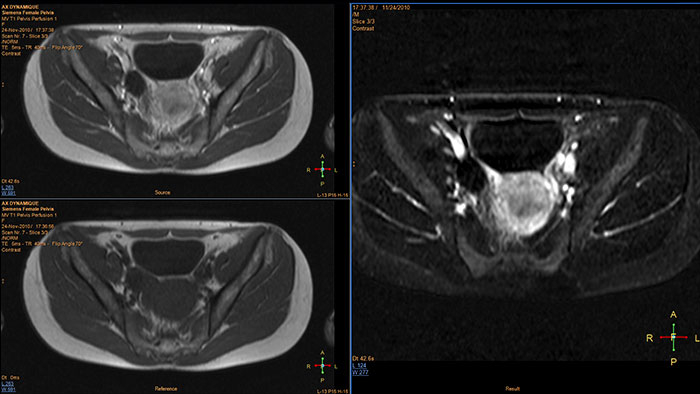

Support in assessing lesions by reviewing blood supply characteristics

MR T1 Perfusion Analysis produces measurements of relative enhancement, maximum enhancement, time to peak (TTP), and wash-in rate. Registration of the source images in the dynamic series can remove motion artifacts, and temporal and spatial smoothing of the input data can be performed to improve SNR.

Benefits